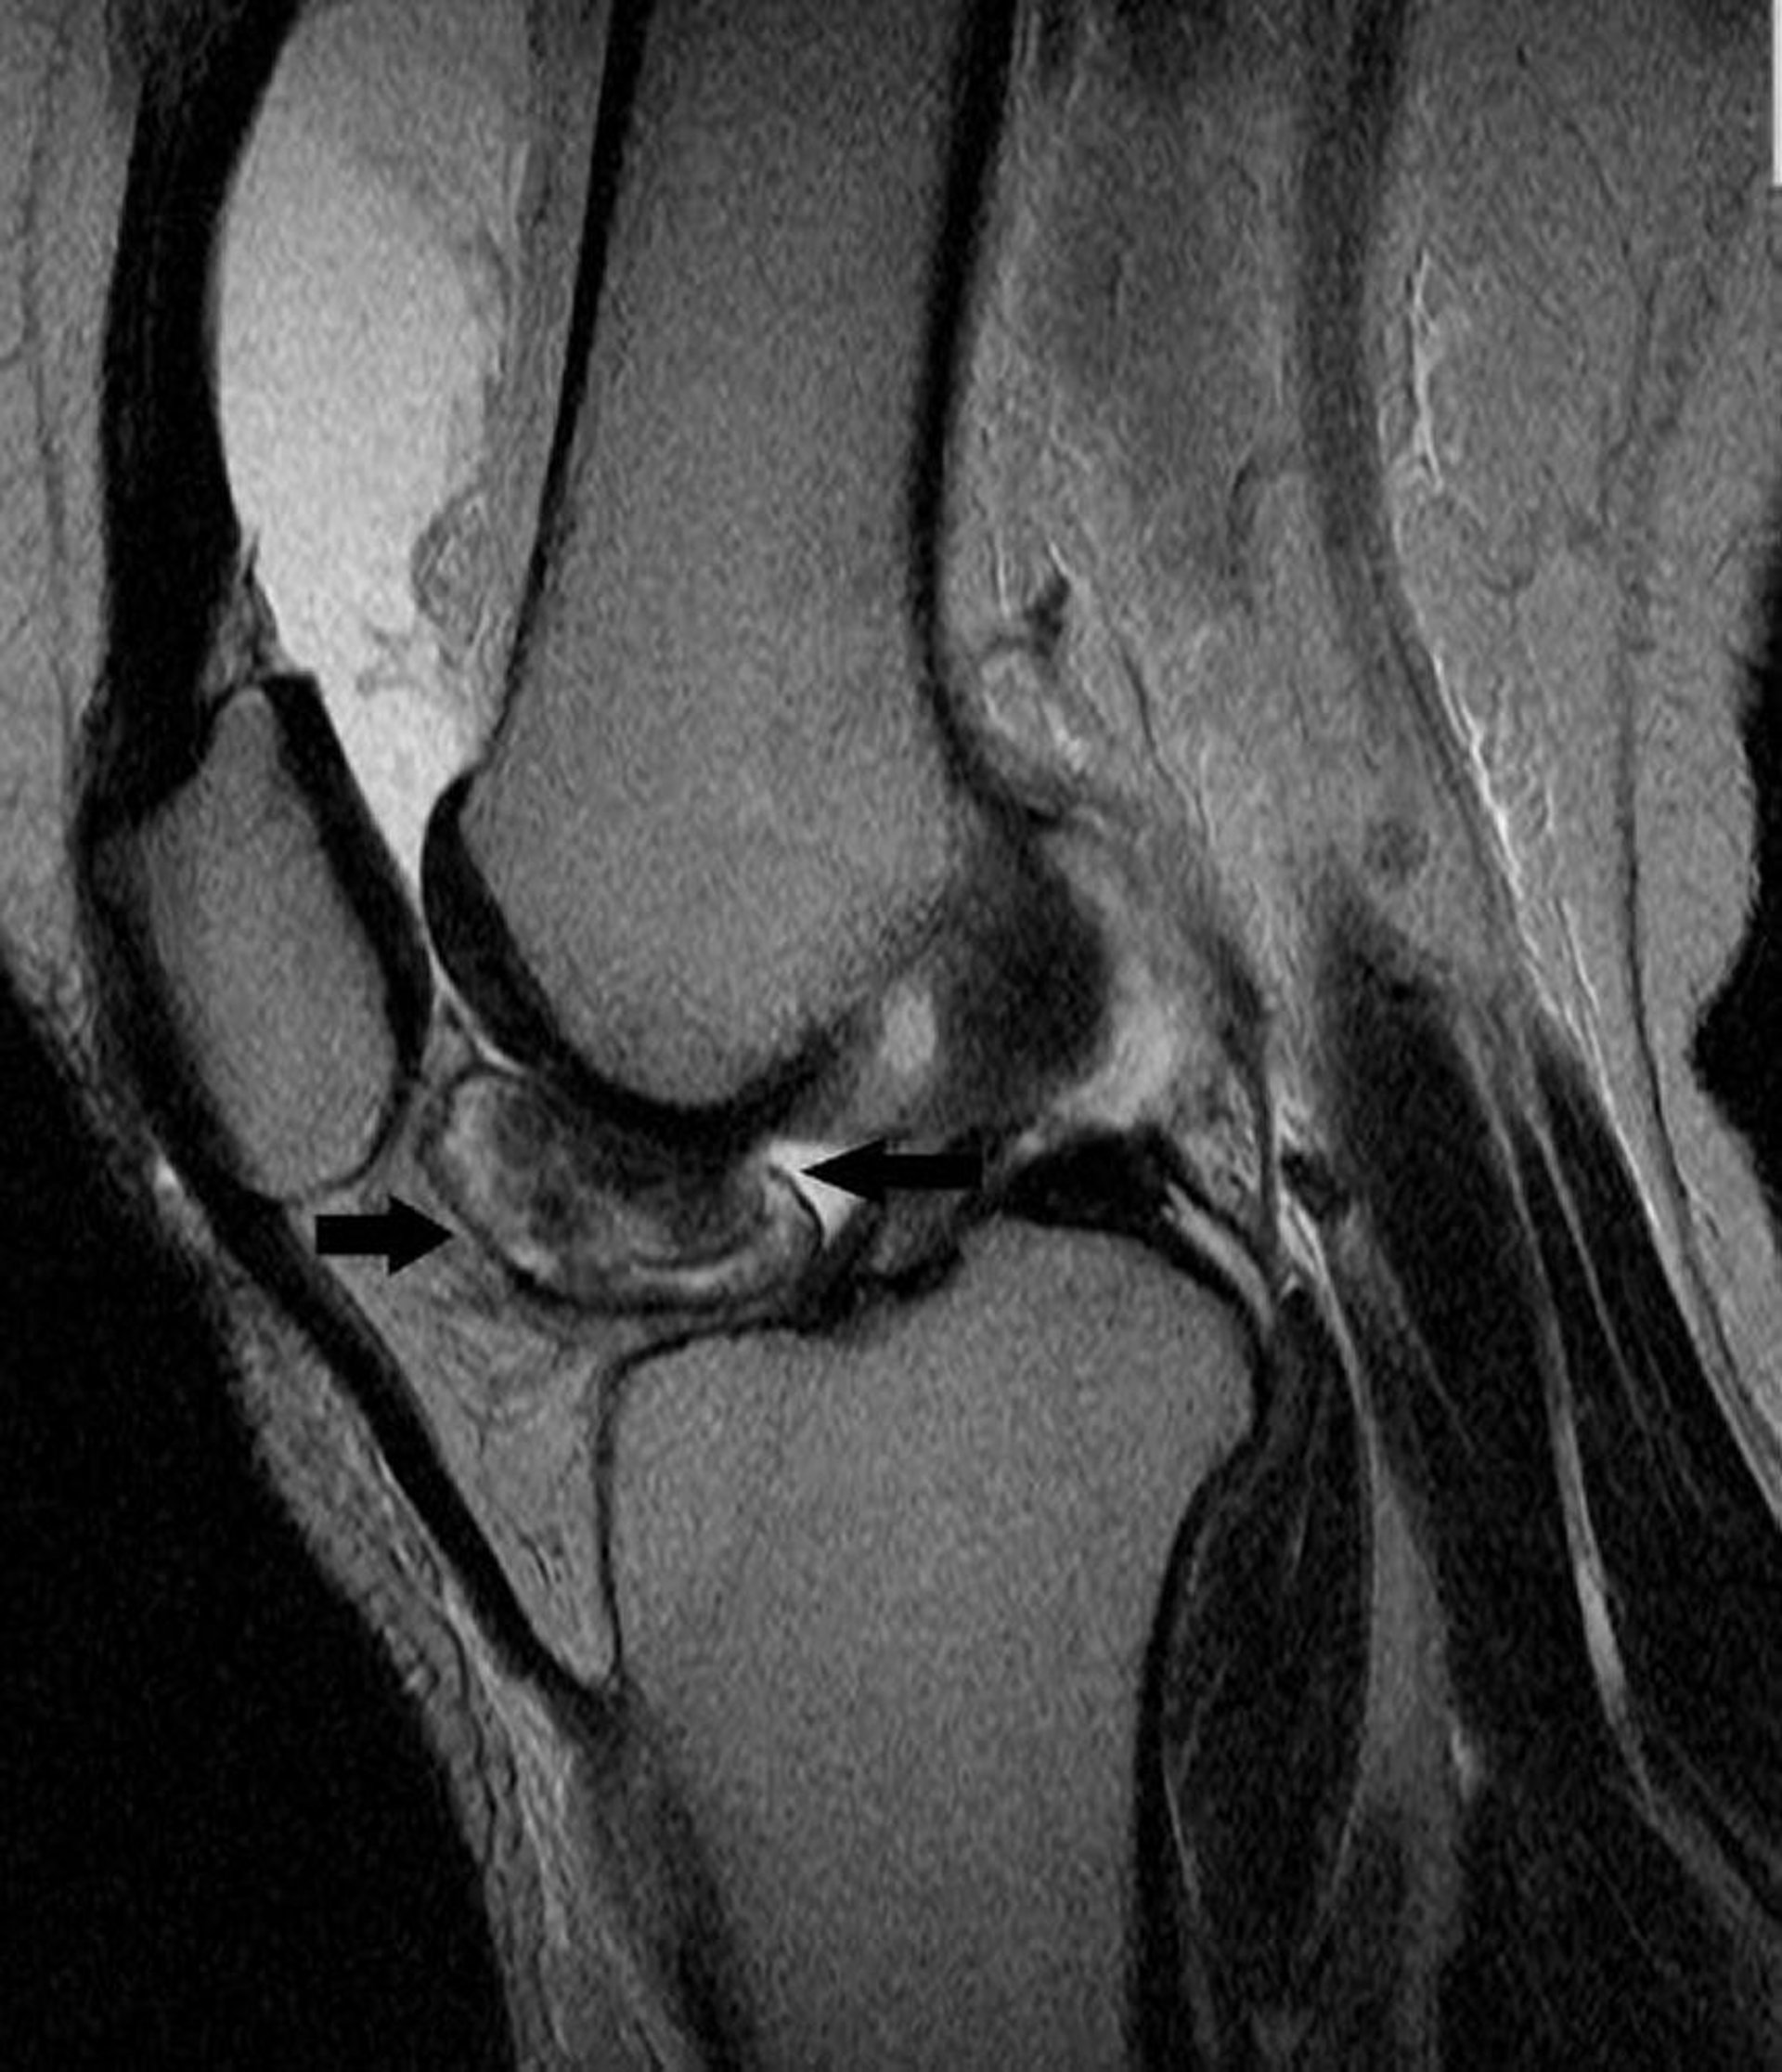

Tumor tenosinovial de células gigantes

Esta RM de rodilla muestra un tumor de células gigantes tenosinoviales en el revestimiento de la articulación de la rodilla (flechas).

Image courtesy of Michael J. Joyce, MD, and Hakan Ilaslan, MD.